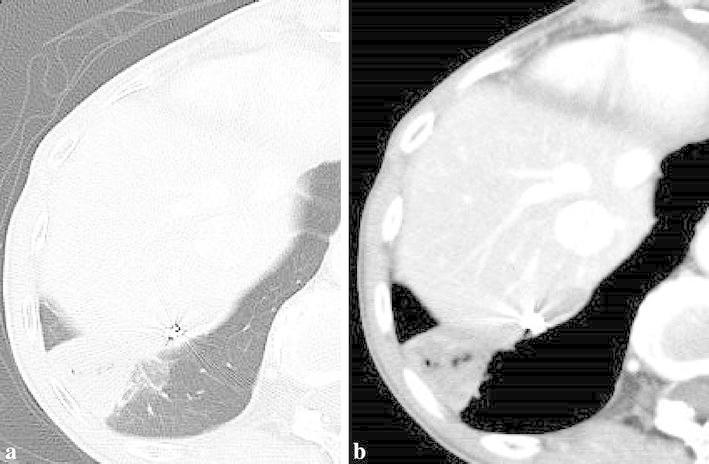

We report a case of a 62-year-old woman with anomalous systemic arterial supply to the basal lung with scimitar syndrome presenting as recurrent hemoptysis. Bronchoscopy revealed normal major bronchial branches without bronchial atresia, indicating that sequestration of the lung was not confirmed. The anomalous drainage of the scimitar vein was to the inferior vena cava, and an anomalous artery from the aorta supplied the right basal lung. There were no findings of pulmonary hypertension and arteriovenous malformation such as an anomalous artery to the scimitar vein. The distal portions of anomalous arteries were embolized using gelatin sponge particles and the proximal portion was embolized using fibered detachable coils. Although a small pulmonary infarction was observed as a complication, the patie nt has not experienced any subsequence recurrence of the hemoptysis during a follow-up period of 6 months.

我们报告一例62岁女性,患有弯刀综合征,表现为反复咯血,其基底肺存在异常体循环动脉供血。支气管镜检查显示主要支气管分支正常,无支气管闭锁,这表明肺隔离症未得到证实。弯刀状静脉异常引流至下腔静脉,一条来自主动脉的异常动脉供应右基底肺。未发现肺动脉高压和动静脉畸形,如弯刀状静脉异常动脉。使用明胶海绵颗粒栓塞异常动脉的远端部分,使用纤维可脱性线圈栓塞近端部分。尽管观察到有小面积肺梗死作为并发症,但在6个月的随访期内患者未再出现咯血。